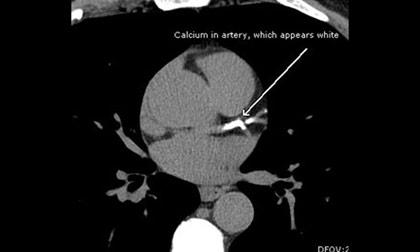

การเกิดโรคเกี่ยวกับหลอดเลือดหัวใจ มีสาเหตุมาจากหลอดเลือดหัวใจมีการอุดตันของการสะสมไขมันในเส้นเลือด หินปูน หรือมีลิ่มเลือดอุดตันที่หลอดเลือดหัวใจ ซึ่งอาจนำไปสู่การเกิดภาวะหัวใจขาดเลือดเฉียบพลัน ทำให้กล้ามเนื้อหัวใจตายในที่สุด

Calcium score report เป็นการตรวจคัดกรองระดับไขมันและหินปูนเกาะที่หลอดเลือด โดยใช้เครื่องเอกซเรย์คอมพิวเตอร์ความเร็วสูง (MDCT 64 Slices) ในการตรวจเพื่อดูทางเดินของหลอดเลือดหัวใจ ว่ามีภาวะเสี่ยงต่อการอุดตันหรือไม่ ซึ่งวิธีนี้เป็นวิธีการตรวจที่ง่ายและรวดเร็วไม่ต้องมีการเตรียมตัวผู้ป่วยให้ยุ่งยาก เพียงแค่ผู้ตรวจกลั้นใจไม่ถึง 10 วินาที และงดเครื่องดื่มที่มีคาเฟอีน งดสูบบุหรี่เป็นเวลา 4 ชั่วโมงก่อนทำการตรวจ สำหรับรายที่ผู้ป่วยมีอัตราการเต้นหัวใจเกิน 90 ครั้งต่อนาทีจำเป็นต้องได้รับยาเพื่อให้หัวใจเต้นเป็นปกติก่อนตรวจ

การรายงานผล Calcium score report เครื่องเอกซเรย์คอมพิวเตอร์ความเร็วสูง (MDCT 64 Slices) จะแสดงถึงค่าตัวเลขตาม NCEP (National Cholesterol Education Program) ดังนี้

Calcium score Presence of Plaque

0 ไม่พบว่าคราบมีไขมันหรือหินปูนเกาะ

1-10 พบว่ามีคราบไขมันหรือหินปูนเกาะเพียงเล็กน้อย

11-100 พบว่ามีคราบไขมันหรือหินปูนเกาะเล็กน้อย

101-400 พบว่ามีคราบไขมันหรือหินปูนเกาะปานกลาง

Over 400 พบว่ามีคราบไขมันหรือหินปูนเกาะมาก